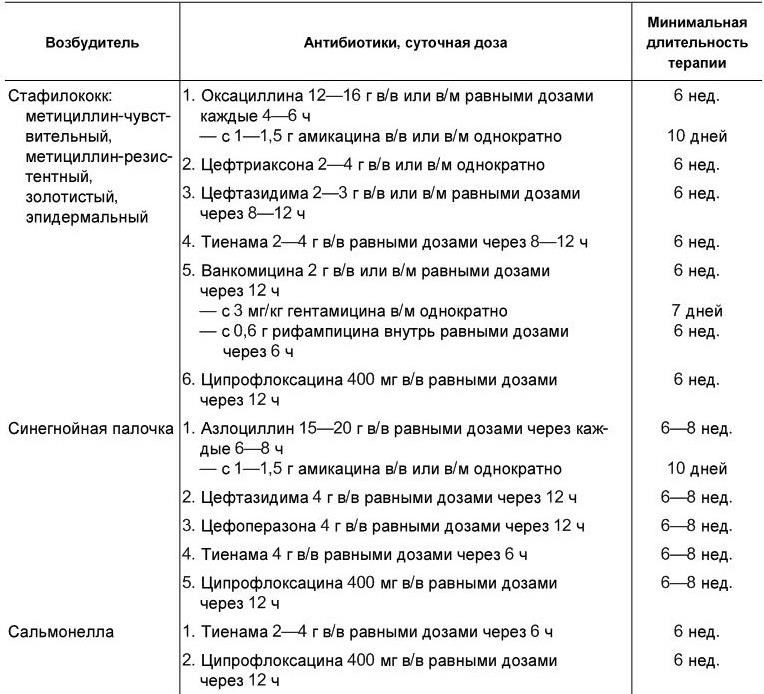

Лечение. Диагноз инфекционного эндокардита или подозрение на его наличие – повод для госпитализации больного. Основа терапии – антибактериальные препараты. Лечение начинают сразу же после взятия крови на посев, а при остром течении – немедленно после постановки диагноза. В первые дни (до получения результатов посева крови) препараты подбираются эмпирически. Обычно исходят из того, что наиболее часто возбудителями являются стрептококки. После получения данных о возбудителе и его чувствительности в терапию вносятся коррективы [Гогин Е. Е., Тюрин В. П., 1997]. Рекомендуется комбинированное введение антибиотиков парентерально в полных терапевтических дозах (табл. 1.13). При грибковых эндокардитах обычно используется амфотерицин В. Он вводится медленно капельно внутривенно в дозе не менее 1,0 г в сутки.

Таблица 1.13

Антибиотики, применяемые при инфекционном эндокардите в зависимости от этиологии болезни

[Гогин Е. Е., Тюрин В. П., 1997]

Длительность терапии определяется исчезновением клинико-лабораторных признаков воспаления, но она не должна быть короче четырех недель даже при самом благоприятном ответе на терапию. Как правило, снижение температурной реакции отмечается через 3 – 7 дней после начала терапии. Длительная антибактериальная терапия может осложняться различными побочными действиями, в том числе ухудшением функционального состояния почек. Нефротоксичность наиболее характерна для гентамицина.